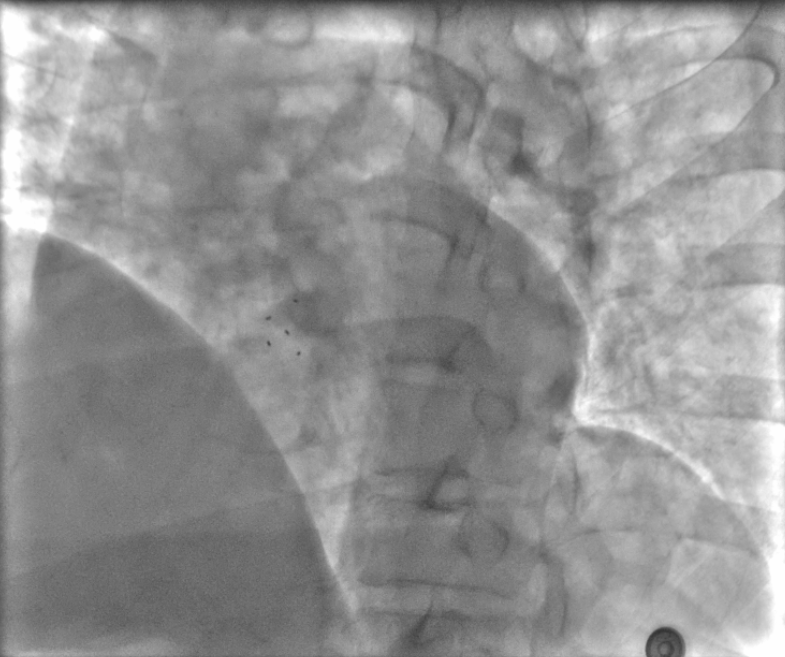

1月27日,姚玉才主任医师、潘金玉主治医师在导管室多模态影像引导下为患者行生物可降解封堵器ASD封堵术。患者取平卧位,常规消毒铺巾,1%利多卡因局麻,超声引导下穿刺右侧股静脉,预置1把Proglide缝合器,置入6F鞘管,在X线透视下、MPA2导管支撑超滑导丝经股静脉-下腔静脉-右房-房缺-左房送至左上肺静脉,交换加硬导丝保留在左上肺静脉,沿加硬导丝送16F输送鞘及扩张管至左房、保留输送鞘在左房、撤出导丝及扩张管、给肝素9000单位,16F输送鞘接装载器,操纵钢缆送生物可降解BDASD I-18封堵器至左房,在X线引导下释放封堵器左房侧伞盘、回拉成型线左盘成型,在经胸超声(TTE)引导下回撤左房侧伞盘至房缺处,多切面评估左房侧伞盘紧贴ASD左房侧,TTE引导下回撤输送鞘释放右侧伞盘,多切面评估确认左右伞盘跨ASD分别位于左右心房、位置固定、无残余分流,回拉成型线封堵器完全锁定,X线LAO45°评估封堵器5个铂环Mark点位置满意,撤出成型线,逆时针旋转钢缆释放封堵器。再次TTE多切面评估(图2)封堵器位置固定、无左向右分流、无心包积液,心电监护无传导阻滞,再次X线LAO45°评估封堵器5个Mark点位置满意、固定(图3)。遂撤出鞘管,用Proglide缝合器缝合股静脉穿刺处,穿刺处无出血及血肿,局部加压包扎,安返至病房。手术过程顺利,患者无不适。

▲图3 X线下LAO45°封堵器5个铂环Mark点位置满意